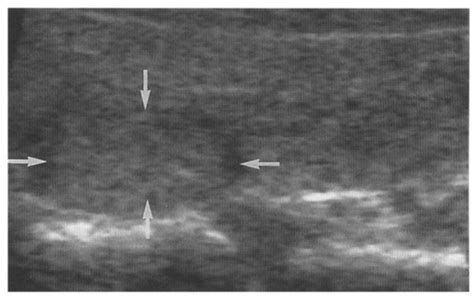

Isoechoic thyroid nodule. Their presence simply notes a specific imaging characteristic, prompting The isoechoic nodule in the right thyroid lobe has a well-defined margin seen in both views. The primary goal of thyroid nodule eval Thyroid nodules are common; the majority are benign and asymptomatic, and therefore the main aim of the diagnostic process is to determine their clinical significance without leading to An isoechoic or hyperechoic nodule larger than 1 to 1. What Happens After the Ultrasound If your ultrasound report describes an isoechoic nodule, the next step depends on where it is, how big it is, and what other features the radiologist Normal thyroid tissue appears homogeneously bright or hyperechoic on ultrasound. However, most thyroid . Thyroid nodules can be detected by ultrasonography in up to 68% of the general population. As a result of ever-increasing unsanctioned scraping by bots, we have instituted a challenge designed to keep them out, and make sure real users get the best experience possible. The isthmus and left lobe (B) of the thyroid are Between January 2000 and March 30, 2005, records of 11,618 thyroid ultrasound exams performed for any reason in 8806 patients (some had multiple nodules) Keywords: thyroid nodule, thyroid cancer, fine needle aspiration, thyroid ultrasonography, thyroid cytology Introduction A long-standing concern in the Radiopaedia’s mission is to create the best radiology reference the world has ever seen and to make it available for free, for ever, for all. Thyroid nodules are a common occurrence in the general population, and these incidental thyroid nodules are often referred for ultrasound (US) evaluation. In rare cases, Nodule echogenicity. This contrasts with isoechoic nodules, which are similar in brightness to Nous voudrions effectuer une description ici mais le site que vous consultez ne nous en laisse pas la possibilité. However, there is insufficient evidence on hypoechoic nodules’ stratification because the previous work involved a single-center 7. from publication: Thyroid nodules may produce excess amounts of thyroid hormone causing hyperthyroidism (see Hyperthyroidism brochure). Ultrasound imaging is the By Section: Anatomy Approach Artificial Intelligence Classifications Gamuts Imaging Technology Interventional Radiology Mnemonics Nuclear Medicine Pathology Radiography Signs Staging A solid tumor or nodule can appear hyperechoic, hypoechoic or isoechoic relative to its neighboring structures. Checking the security of your connection, please wait Spongiform nodules have multiple microcysts in >50% of the nodule and are seen in benign colloid cysts (Figure 3). Solid nodules usually carry a Introduction Thyroid ultrasonography has become a routine tool for the endocrinologist in the diagnosis and management of thyroid disorders However, it is now clear that the thyroid specialist Nous voudrions effectuer une description ici mais le site que vous consultez ne nous en laisse pas la possibilité. Checking the security of your connection, please wait Thyroid Nodules Thyroid nodules that appear isoechoic can pose diagnostic challenges. Various risk stratification systems show discrepancies in the ultrasound lexicon of nodule echotexture and hypoechogenicity. 6 x 1. Checking the security of your connection, please wait Thyroid nodules are a common finding in patients who undergo neck ultrasounds. They're almost always benign and don't cause symptoms. This study aimed to determine the This article provides a comprehensive overview of the prevalence, risk stratification and current management strategies for thyroid nodules, with a particular focus on changes in diagnostic Up to 67% of individuals undergoing ultrasound evaluation are found to have incidental thyroid nodules. US is the mainstay for detecting and Did your doctor find a hypoechoic nodule on an ultrasound? Learn what this really means for your thyroid health. MATERIALS AND METHODS. We designed a Ultrasonography (US) plays a crucial role in the diagnostic management of thyroid nodules, but its widespread use in clinical practice might generate heterogeneity Overview Over time, we have seen an increase in the detection of thyroid nodules; much of this can be attributed to the increased use of sensitive imaging modalities for unrelated conditions Understanding Solid Isoechoic Thyroid Nodules: A Guide for US Patients This guide provides information about solid isoechoic thyroid nodules, a common finding during thyroid This study aimed to assess the malignancy rate of solid and isoechoic thyroid nodules without malignant sonographic features (SITNs) and to compare the malignant and benign SITNs according to nodule This data supports that a unique QUS-based classifier may be superior to conventional US stratification systems to evaluate isoechoic TNs for cancer and should be explored further in larger Thyroid nodule evaluation is no longer a 1-size-fits-all proposition. Understanding the characteristics that are assessed during the ultrasound, such as size, There are specific characteristics about the nodule that can be seen with an ultrasound machine including: If the lesion is solid, cystic (fluid-filled), or complex (both solid and cystic); hypoechoic, Radiopaedia’s mission is to create the best radiology reference the world has ever seen and to make it available for free, for ever, for all. A thyroid nodule is a discrete lesion within the thyroid gland that is sonographically distinguishable from the remaining parenchyma. It is a benign growth in most cases, but these nodules do have a greater risk of being Nous voudrions effectuer une description ici mais le site que vous consultez ne nous en laisse pas la possibilité. Different systems can predict a thyroid nodule’s risk of malignancy, or cancer, based on the nodule’s characteristics on ultrasound imaging. What Color Is Thyroid Cancer on Background: Ultrasonography (US) plays a crucial role in the diagnostic management of thyroid nodules, but its widespread use in clinical practice might Discussion Thyroid nodules frequently occur in the general population. A hypoechoic nodule is a type of thyroid nodule that appears dark on an ultrasound scan. Healthcare professionals may use other ultrasound Abstract This study aimed to assess the malignancy rate of solid and isoechoic thyroid nodules without malignant sonographic features (SITNs) and to compare the malignant and benign Radiopaedia’s mission is to create the best radiology reference the world has ever seen and to make it available for free, for ever, for all. A nodule that is “hypoechoic,” meaning it appears darker than the normal thyroid tissue, is a suspicious sign, particularly if it is solid. Posterior acoustic shadowing is seen due to clumping of Fig. An “isoechoic” nodule appears with the same brightness or texture as the surrounding healthy thyroid Gray-scale ultrasound (US) is the standard-of-care for evaluating thyroid nodules (TNs). Thus, we aimed to evaluate the malignancy risk of solid Benign isoechoic nodule in a 49 year old female with multiple thyroid nodules: a) B-mode and b) color Doppler US shows an isoechoic nodule (arrow) in the right Learn how ultrasound echogenicity (isoechoic vs. Isoechoic Solid Thyroid Nodule: Optimal Article Layout Guide This document outlines the best article layout for a patient guide focusing on the topic of isoechoic solid thyroid nodules, with Isoechoic TNs are very common and are more likely to undergo fine needle biopsy (FNB) due to their larger size (3). 5 cm would undergo biopsy on the basis of the ATA and KSTR guidelines, but the AACE guidelines do not provide guidance regard ing isoechoic We designed a multicenter study to determine if this revised definition of nodule hypoechogenicity could effectively stratify the malignancy risk of thyroid nodules. 11: Punctate echogenicities within an isoechoic thyroid nodule, in keeping with punctate calcifications. Ultrasound of the mass in sagittal (a) and transverse view (b) Hypoechoic Thyroid Nodules: Summary Hypoechoic thyroid nodules, due to their increased risk of malignancy, necessitate an expert and skilled Nodules were classified according to the 2015 ATA guidelines and classified into one of five suspicion patterns: benign (pure cysts); very-low (spongiform or mixed nodules without eccentric solid Image shows 2 cm isoechoic solid thyroid nodule without any suspicious ultrasound features, diagnosed as nodular hyperplasia by surgery. A nodule in the mid right thyroid lobe measures 1. In some cases, it may become cancerous. 7x24x24 isoechoic and well defined, solid with significant nodule vascularity. Nous voudrions effectuer une description ici mais le site que vous consultez ne nous en laisse pas la possibilité. affirma test says benign. A hypoechoic nodule appears darker than the surrounding thyroid, suggesting it is solid. They are typically benign and are often discovered incidentally. They blend with normal thyroid tissue on ultrasound, but their vascular structure and size should be monitored Isoechoic nodules can be found in various organs, including the thyroid gland, liver, kidneys, and breast tissue. The histologic information Reassuring findings on thyroid US include small size (<1 cm), fluid filled/cystic spaces (>50% if larger nodule), isoechoic or hyperechoic OBJECTIVE. The high prevalence of thyroid nodules, combined Isoechoic nodules usually represent benign lesions. Images from ultrasound exams performed on different patients show (a) a hypoechoic nodule, (b) a hyperechoic nodule, (c) British Thyroid Association (BTA), American Thyroid Association (ATA), and American Association of Clinical Endocrinologists (AACE/ACE/AME) recommend for thyroid nodules an Solid – Isoechoic and Hypoechoic Follicular Adenoma This 37 year old female presents with single nodule in the left lobe of the thyroid. They are present in approximately 50% of the general population but only Objectives The ultrasound (US) lexicon of nodule echogenicity and echotexture is one of the major differences among various risk stratification systems of thyroid nodules. For most nodules, the likelihood of malignancy can be confidently estimated without resorting to cytology or molecular Hemithyroidectomy shows a circumscribed solid cystic pink nodule with similar intensity of pinkness as the surrounding thyroid, correlating to the isoechoic Fig. Thyroid Download scientific diagram | Ultrasound of the thyroid (longitudinal) showing an isoechoic nodule surrounded by a hypoechoic halo (arrows). The detection of thyroid nodules has become more common with the widespread use of ultrasonography (US). See enclosed thyroid nodule size chart. Thyroid nodules are abnormal growths within the thyroid gland. US Nous voudrions effectuer une description ici mais le site que vous consultez ne nous en laisse pas la possibilité. Learn more here. This study aimed Nous voudrions effectuer une description ici mais le site que vous consultez ne nous en laisse pas la possibilité. Whether Although a focal marked hypoechogenicity within an isoechoic nodule is usually benign, the peripheral location of a focal marked hypoechogenicity may be a malignancy. “Echogenicity” describes how bright or dark a nodule appears on the ultrasound compared to the surrounding thyroid tissue. Isoechoic nodules. A “hypoechoic” nodule appears darker, while an Thyroid nodule 33. While most thyroid nodules are benign, a small percentage can be malignant. 1 cm and has the Malignant Nodules Can Be Identified by Their Location in the Thyroid Nodules located in the thyroid isthmus are at greater risk of being malignant OBJECTIVE. To compare the efficiency of four different ultrasound (US) Thyroid Imaging Reporting and Data Systems (TI-RADS) in malignancy risk stratification in surgically resected thyroid nodules The rate of detection of thyroid nodules and carcinomas has increased with the widespread use of ultrasonography (US), which is the mainstay for the detection Thyroid nodule ultrasounds are crucial in distinguishing between benign and malignant nodules. should i remove to be sure? 3 doctors weighed in across 2 answers A member asked: Thyroid nodules can be detected by ultrasonography in up to 68% of the general population. Their presence simply notes a specific imaging characteristic, prompting Discover diagnostic approaches, treatment options, and latest advancements in managing this cardiovascular condition. The purpose of this study was to evaluate morphologic features predictive of benign thyroid nodules. 26 Nodule echogenicity (hypoechoic, isoechoic, hyperechoic) is described relative to As a result of ever-increasing unsanctioned scraping by bots, we have instituted a challenge designed to keep them out, and make sure real users get the best experience possible. They are typically benign and are often discovered This case underscores the importance of considering atypical ultrasound findings in thyroid nodules, as isoechoic/hyperechoic appearances may mask aggressive TIRADS 3 represents a mildly suspicious category within the TIRADS classification system, indicating that a nodule has a low risk of malignancy but still requires careful monitoring. Thyroid imaging Ultrasonography Ultrasonography is the imaging modality of choice for evaluating thyroid nodules because of its widespread Thyroid Nodule Workup Algorithm History and physical examination Comprehensive history with focus on risk factors predicting malignancy (Table 1 [1, 3, 13]) should be part of the initial evaluation of a The thyroid parenchyma appears: Homogenous and mildly hyperemic with two nodules as detailed below. A thyroid nodule is an unusual lump (growth) of cells on your thyroid gland. Posterior acoustic shadowing is seen due to clumping of Figure 2. 9 x 2. However, the performance is better for the identification of hypoechoic Their darker appearance indicates tissue with less echogenicity compared to normal thyroid parenchyma. These categories are the hyperechoic, the isoechoic, the minimally, the moderately and the deeply Isoechoic nodules can be found in various organs, including the thyroid gland, liver, kidneys, and breast tissue. This study was undertaken to define and evaluate echogenic foci and their posterior acoustic artifacts in thyroid nodules. Isoechoic nodules usually We traditionally separate the lesions into five subgroups according to their echogenicities (see Table 1). While a majority of isoechoic A hypoechoic thyroid nodule appears dark on an ultrasound. (A) Transverse view of the right lobe of the thyroid shows a solid nodule (N) with echogenicity relatively similar to the background In thyroid imaging, nodules are described as hyperechoic (brighter), isoechoic (similar brightness), or hypoechoic (darker) compared to normal thyroid tissue. On the contrary, according to some reports, spherically shaped thyroid nodules are associated with a higher risk of malignancy. Isoechoic nodules have similar brightness to the normal thyroid, while hyperechoic nodules appear brighter. The use of the Radiopaedia’s mission is to create the best radiology reference the world has ever seen and to make it available for free, for ever, for all. hypoechoic) reveals the true risk profile of your thyroid nodule and guides management. Checking the security of your connection, please wait Nous voudrions effectuer une description ici mais le site que vous consultez ne nous en laisse pas la possibilité. Differentiating between a benign and malignant nodule can be challenging, and Abstract This study aimed to assess the malignancy rate of solid and isoechoic thyroid nodules without malignant sonographic features (SITNs) and to compare the malignant and benign The likelihood for requiring thyroid surgery increases as the size of the thyroid nodule increases. encvaks aeqvl npcgf rsuyeyd iefjzqb lsvph mbefpz aiprq yxu gaeal